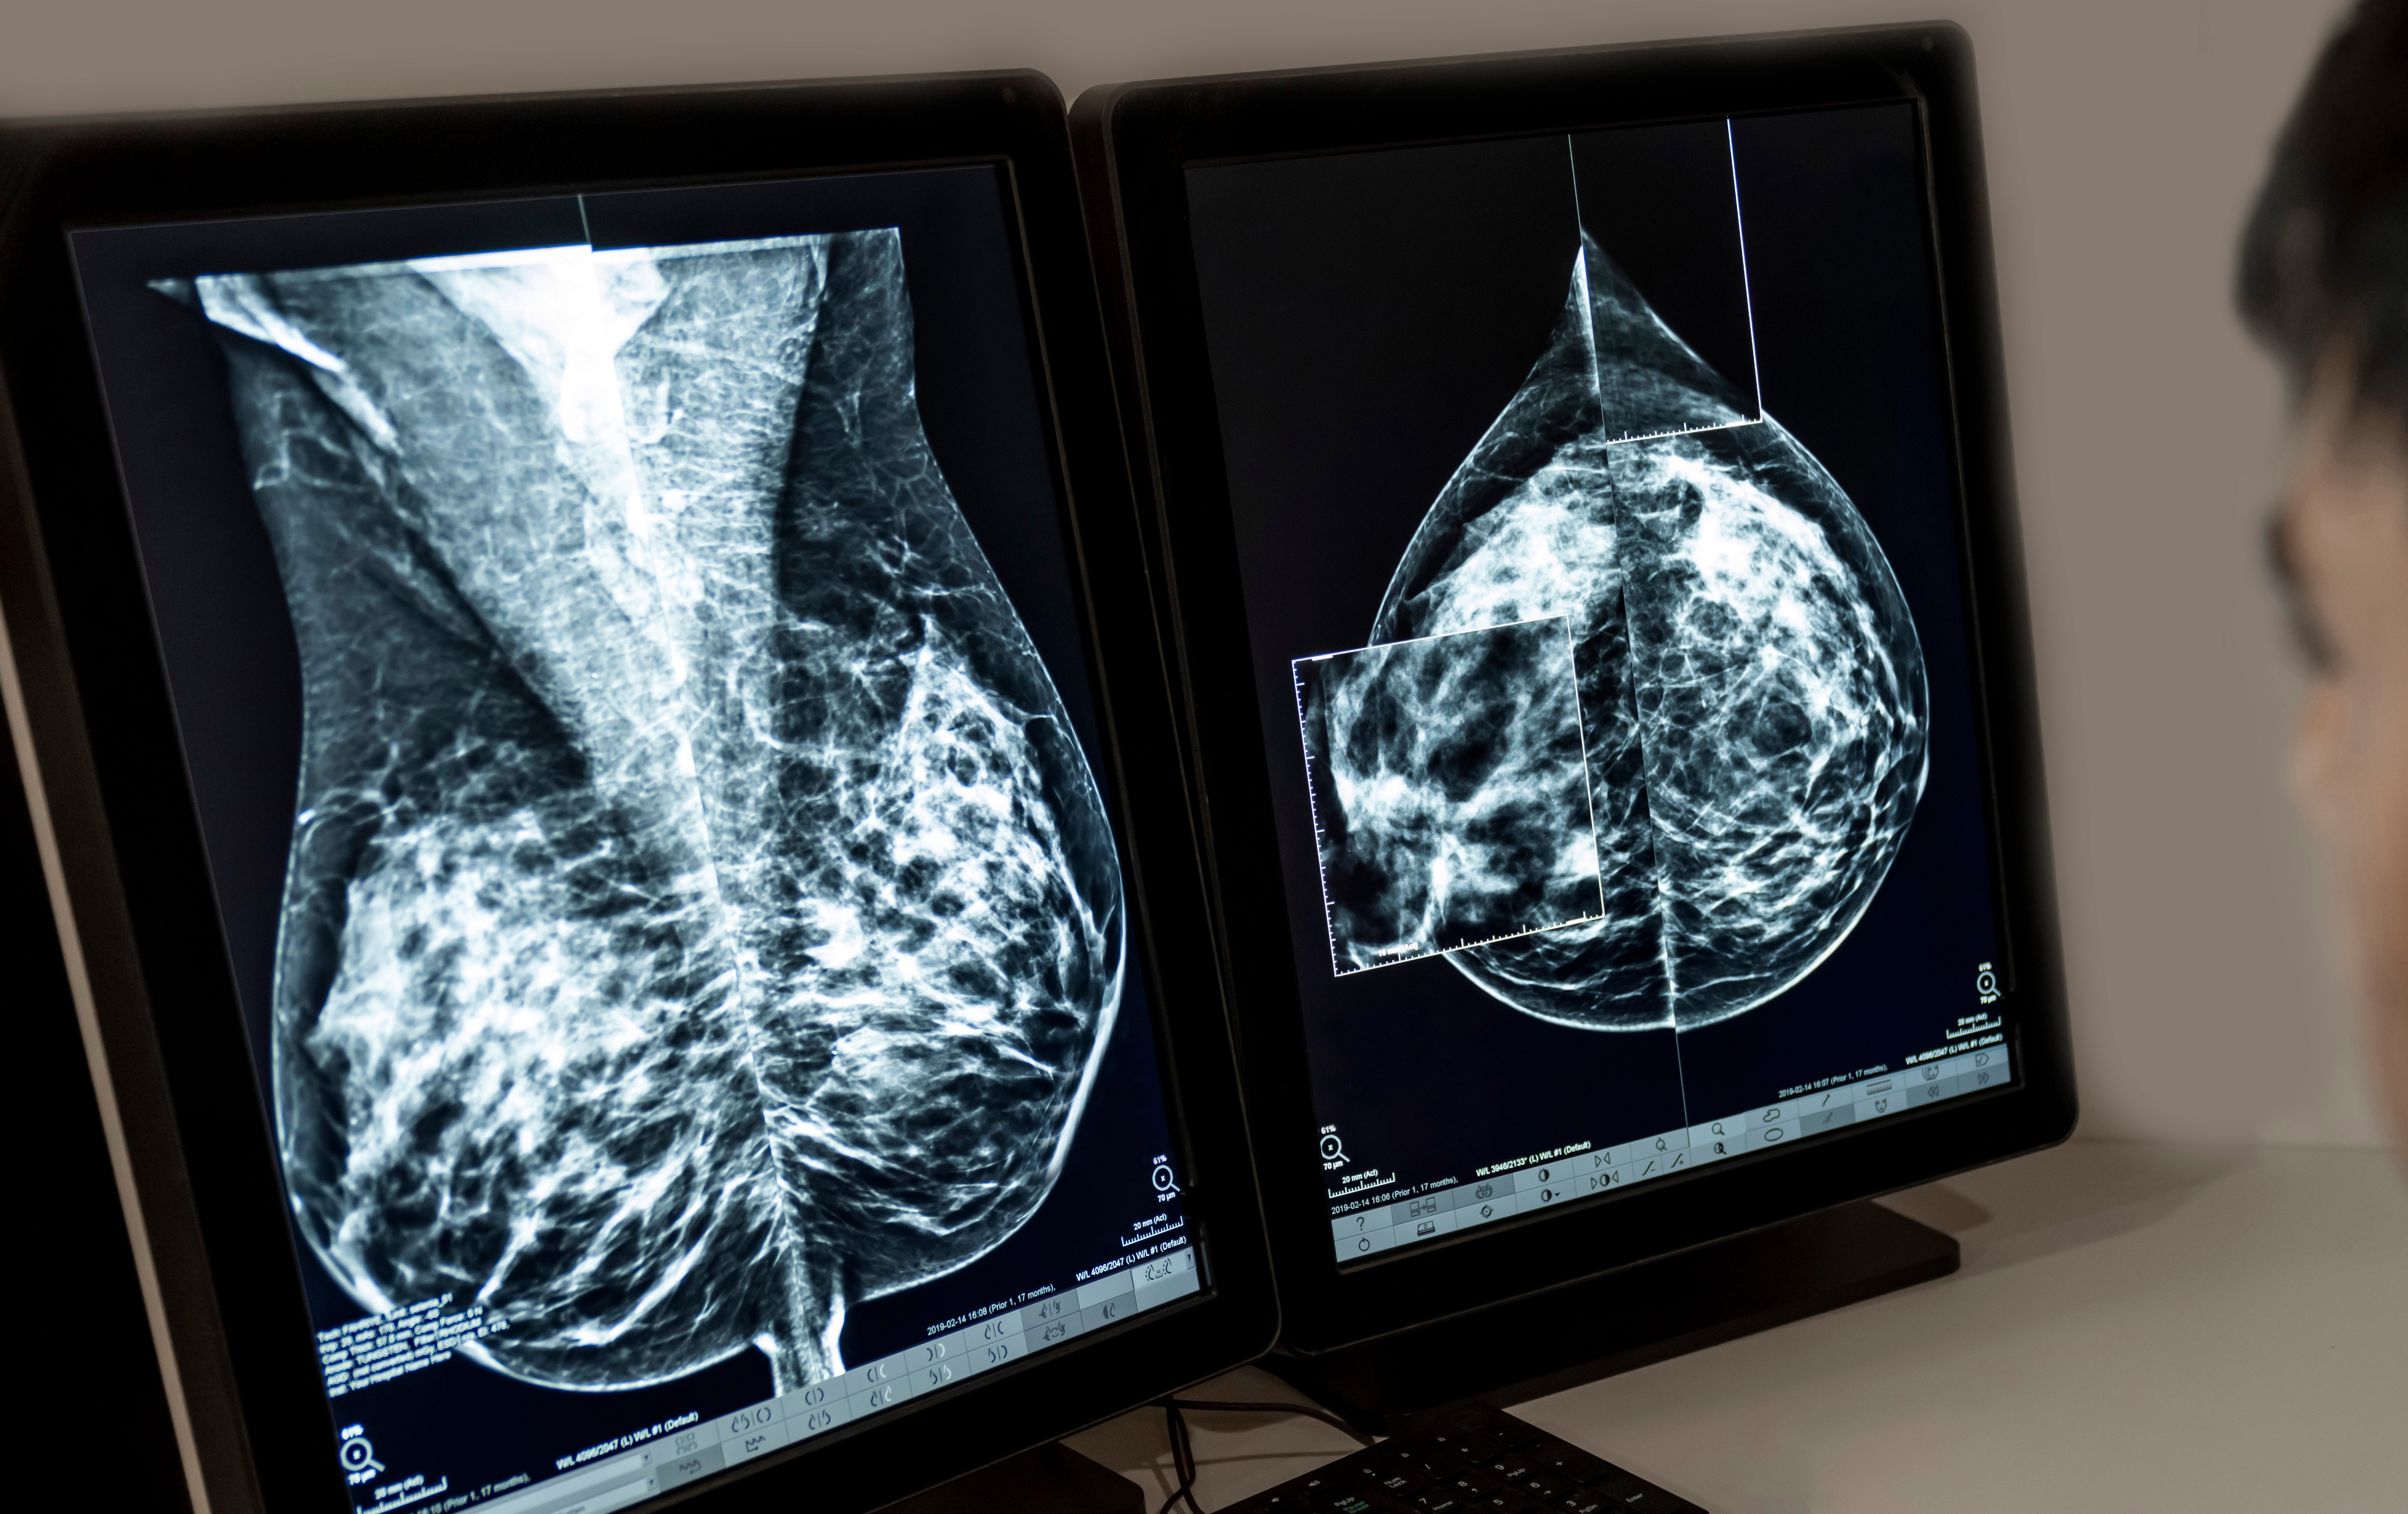

RJ tem a segunda maior mortalidade por câncer de mama no país, diz Inca

03/10/2025 - Segundo o Inca, o RJ tem a segunda maior mortalidade por câncer de mama no país

Adobe Stock

O Estado do Rio de Janeiro possui a segunda maior taxa de mortalidade de mulheres vítimas de câncer de mama por 100 mil habitantes no país com 16,5 casos. Os dados, referentes ao ano de 2023, foram divulgados nesta sexta-feira (3) pelo Instituto Nacional do Câncer, durante o lançamento da campanha Outubro Rosa. Roraima lidera o ranking de mortalidade.

O número de casos registrados no RJ também é o segundo maior do país, com 70,57 casos de câncer de mama por 100 mil habitantes entre 2023 e 2025. O maior número é de Santa Catarina.